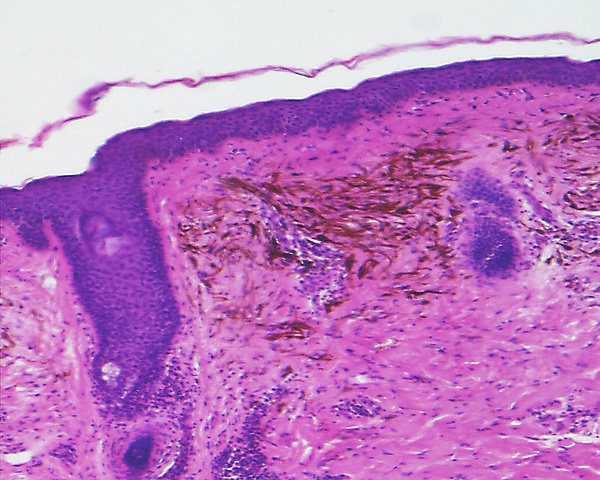

Основным методом подтверждения диагноза голубого невуса является гистологическое исследование биопсийного материала изменённого участка кожи. При простой форме выявляется узловатое скопление слабо пигментированных веретеновидных меланоцитов и выраженных дендритных меланоцитов, расположенных между утолщёнными коллагеновыми волокнами. Часто обнаруживаются меланофаги. Митотическая активность для этой формы нехарактерна[1][5]. Наблюдаются явления склероза в строме[9].

Клеточная форма представлена плотными фестончатыми скоплениями веретеновидных или овоидных меланоцитов, формирующих тяжи и гнёзда, которые могут распространяться в подкожно-жировую клетчатку. Для неё типично более выраженное клеточное строение при отсутствии выраженной цитологической атипии и некроза. Возможны редкие митозы. Часто определяется компонент простой формы внутри клеточного невуса[5].